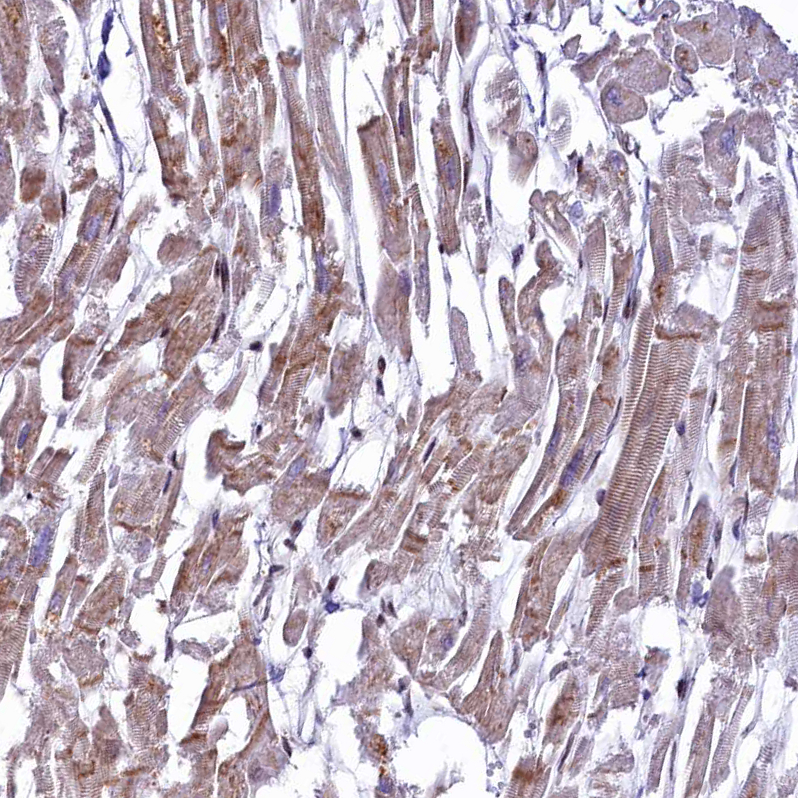

Immunohistochemical staining of human Kidney shows moderate cytoplasmic positivity in cells in tubules.